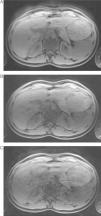

ResultadosLa adquisición en apnea proporcionó mejor calidad de imagen y menos artefactos que la adquisición con respiración libre. La tasa de artefactos fue mayor para FR más altos. La mejor calidad se obtuvo con secuencias en apnea con un FR=2. Un FR=4 presentó tasas menores pero diagnósticas (p=0,004). La severidad de los artefactos, en especial el granulado de los píxeles (p=0,004), hizo que las secuencias con un FR=6 no fueran diagnósticas. Ninguna de las secuencias obtenidas con respiración libre fue diagnóstica.

ResultsImage quality and extent of artifacts were better with breath hold than with free breathing acquisitions. The rate of artifacts increased with higher RF. The best quality was acquired with breath hold sequence using RF=2. RF=4 had lower but diagnostic rates (P=.004). The severity of artifacts, mainly pixel graininess (P=.004), rendered sequences with RF=6 non-diagnostic. All sequences were non-diagnostic in free breathing acquisitions.